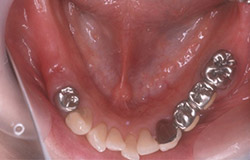

インプラントで噛み合わせの再構成を伴った症例。

治療後のメンテナンスを行わないと

周囲炎になるリスクあり。